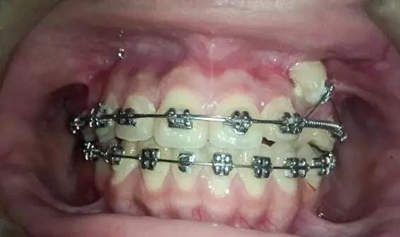

那好吧還是采用輔弓增加支抗,經(jīng)濟(jì)適用,也便與操作,0.8不銹鋼絲彎制,進(jìn)行熱處理,增加其彈力。

結(jié)扎固定

考慮了一下沒有采用其他輔助裝置和種植支抗,還是采用輔弓增加支抗,經(jīng)濟(jì)適用,也便與操作,0.8不銹鋼絲彎制,進(jìn)行熱處理,增加其彈力。

結(jié)扎固定后開始牽引尖牙向遠(yuǎn)中,